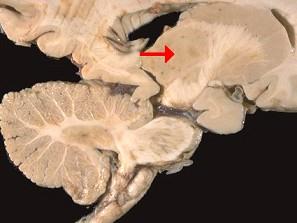

问题 如图箭头所示为大脑哪个部位 ( )

选项 A、松果体 B、中脑导水管 C、豆状核 D、尾状核 E、丘脑 一、单项选择题

答案 E